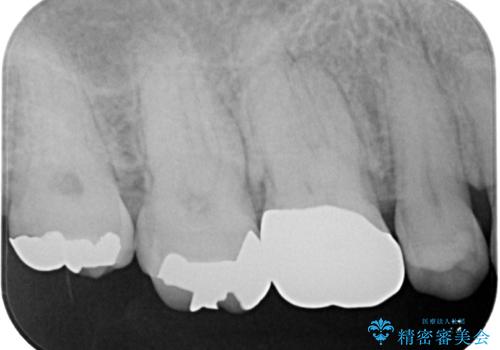

咬み合わせが非常に強く、見た目よりも機能と安定性を重視したいとのことで、PGAクラウン(白金加金合金クラウン)にて補綴する治療計画となりました。

PGAクラウンにしたことで咬み心地に全く違和感がなく、気にされていた審美面も、奥歯でありそれほど目立たないこともありますが、白金加金の色を気に入っていただけたので、患者様には大変満足していただけました。